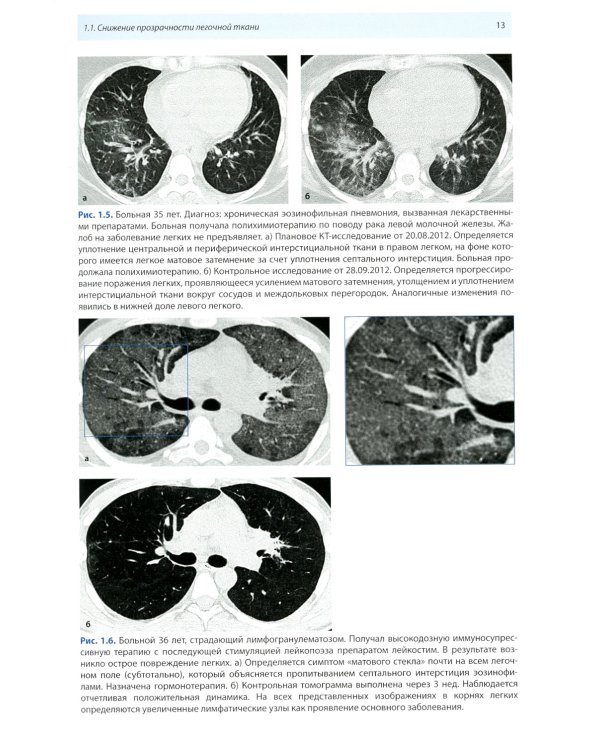

Книга составлена из двух разделов. В первом (глава 1) описаны основные симптомы патологии легких, выявляемые при КТ. Каждый из них представлен с позиции отображающих его морфологических изменений. В краткой форме описаны заболевания, проявляющиеся конкретным симптомом. Второй раздел книги состоит из трех глав, в которых отражены современные взгляды на наиболее часто встречающуюся патологию легких (пневмония, туберкулез, рак) и показаны возможности КТ в выявлении этих заболеваний. Издание предназначено для врачей лучевой диагностики, терапевтов, интернов и студентов старших курсов, интересующихся проблемами рентгенологии.| Издательство | МЕДпресс-информ |